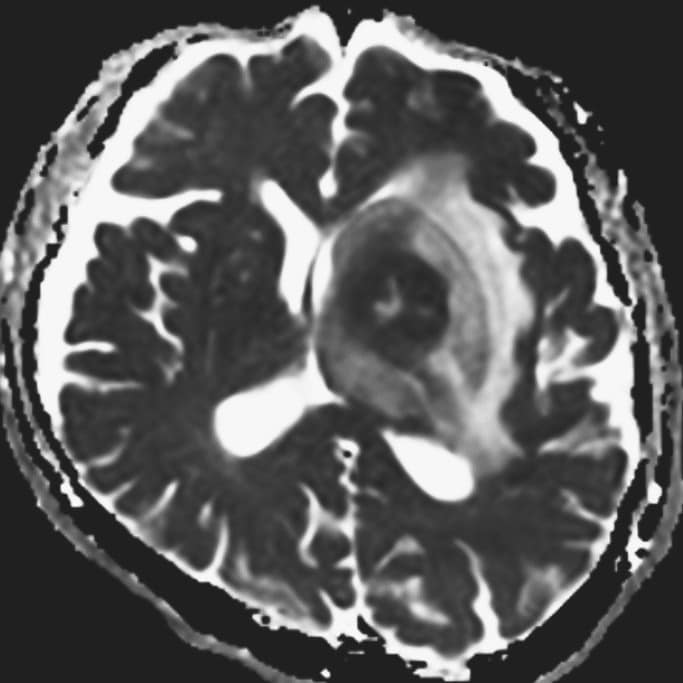

認知機能低下、行動異常、右不全片麻痺の進行を認め、頭蓋内の精査目的に頭部MRIが施行された。左大脳基底核に腫瘍性病変および腫瘍周囲浮腫の所見を認めた。同病変は、造影T1強調像画像では極めて淡い軽度の造影効果を示し、拡散強調画像では軽度の高信号、ADC画像では低信号を示した。診断確定のため生検手術を行った。生検手術1週間後に頭部MRIを施行すると、術前に施行した頭部MRIとは所見が変化し、左大脳基底核の病変は造影T1強調画像では明瞭な造影効果を認め、拡散強調画像でも高信号の増強、ADC画像では低信号を示した。病理組織学的診断は中枢神経系原発悪性リンパ腫であった。そのためR-MPV療法(リツキシマブ、メトトレキサート、プロカルバジン、ビンクリスチン)を施行した。R-MPV療法の経過中の頭部MRIでは、左大脳基底核の病変は縮小傾向を認め、それに伴い初診時に認めていた認知機能低下、行動異常、右不全片麻痺は改善傾向にあり、良好に経過している。